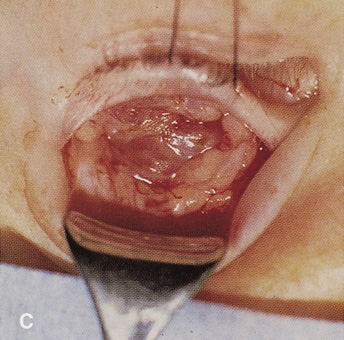

TRANSANTRAL ORBITOTOMY

Lesions in the subperiosteal space that involve the orbital floor and roof of the maxillary sinus can be approached through an intraoral incision in the buccal sulcus above the upper canine incisors (Fig. 19). Dissection is carried through mucosa and soft tissue to the periosteum over the face of the maxilla. Dissection is carried superiorly in the subperiosteal plane to just below the inferior orbital rim. Care must be taken to identify the infraorbital nerve as it exits the foramen just below the rim. Osteotomies then are made in the face of the maxilla, and the underlying maxillary sinus is exposed. The sinus mucosa is excised and the roof of the sinus exposed in this fashion. Removal of the sinus roof (the orbital floor) allows exposure of the inferior periorbita. Care must be taken to avoid damage to the infraorbital nerve that runs within the bone of the floor. The inferior rectus muscle is encountered immediately above the periorbita, and it must be protected and retracted during deeper orbital dissection.

Fig. 19. Transantral inferior orbitotomy. The orbital floor (A) (roof of maxillary sinus) is exposed by an incision in the buccal sulcus and removal of the anterior face of the maxillary bone. The infraorbital nerve (B) traverses the floor of the orbit and exits on the face of the maxilla from the infraorbital foramen (C).